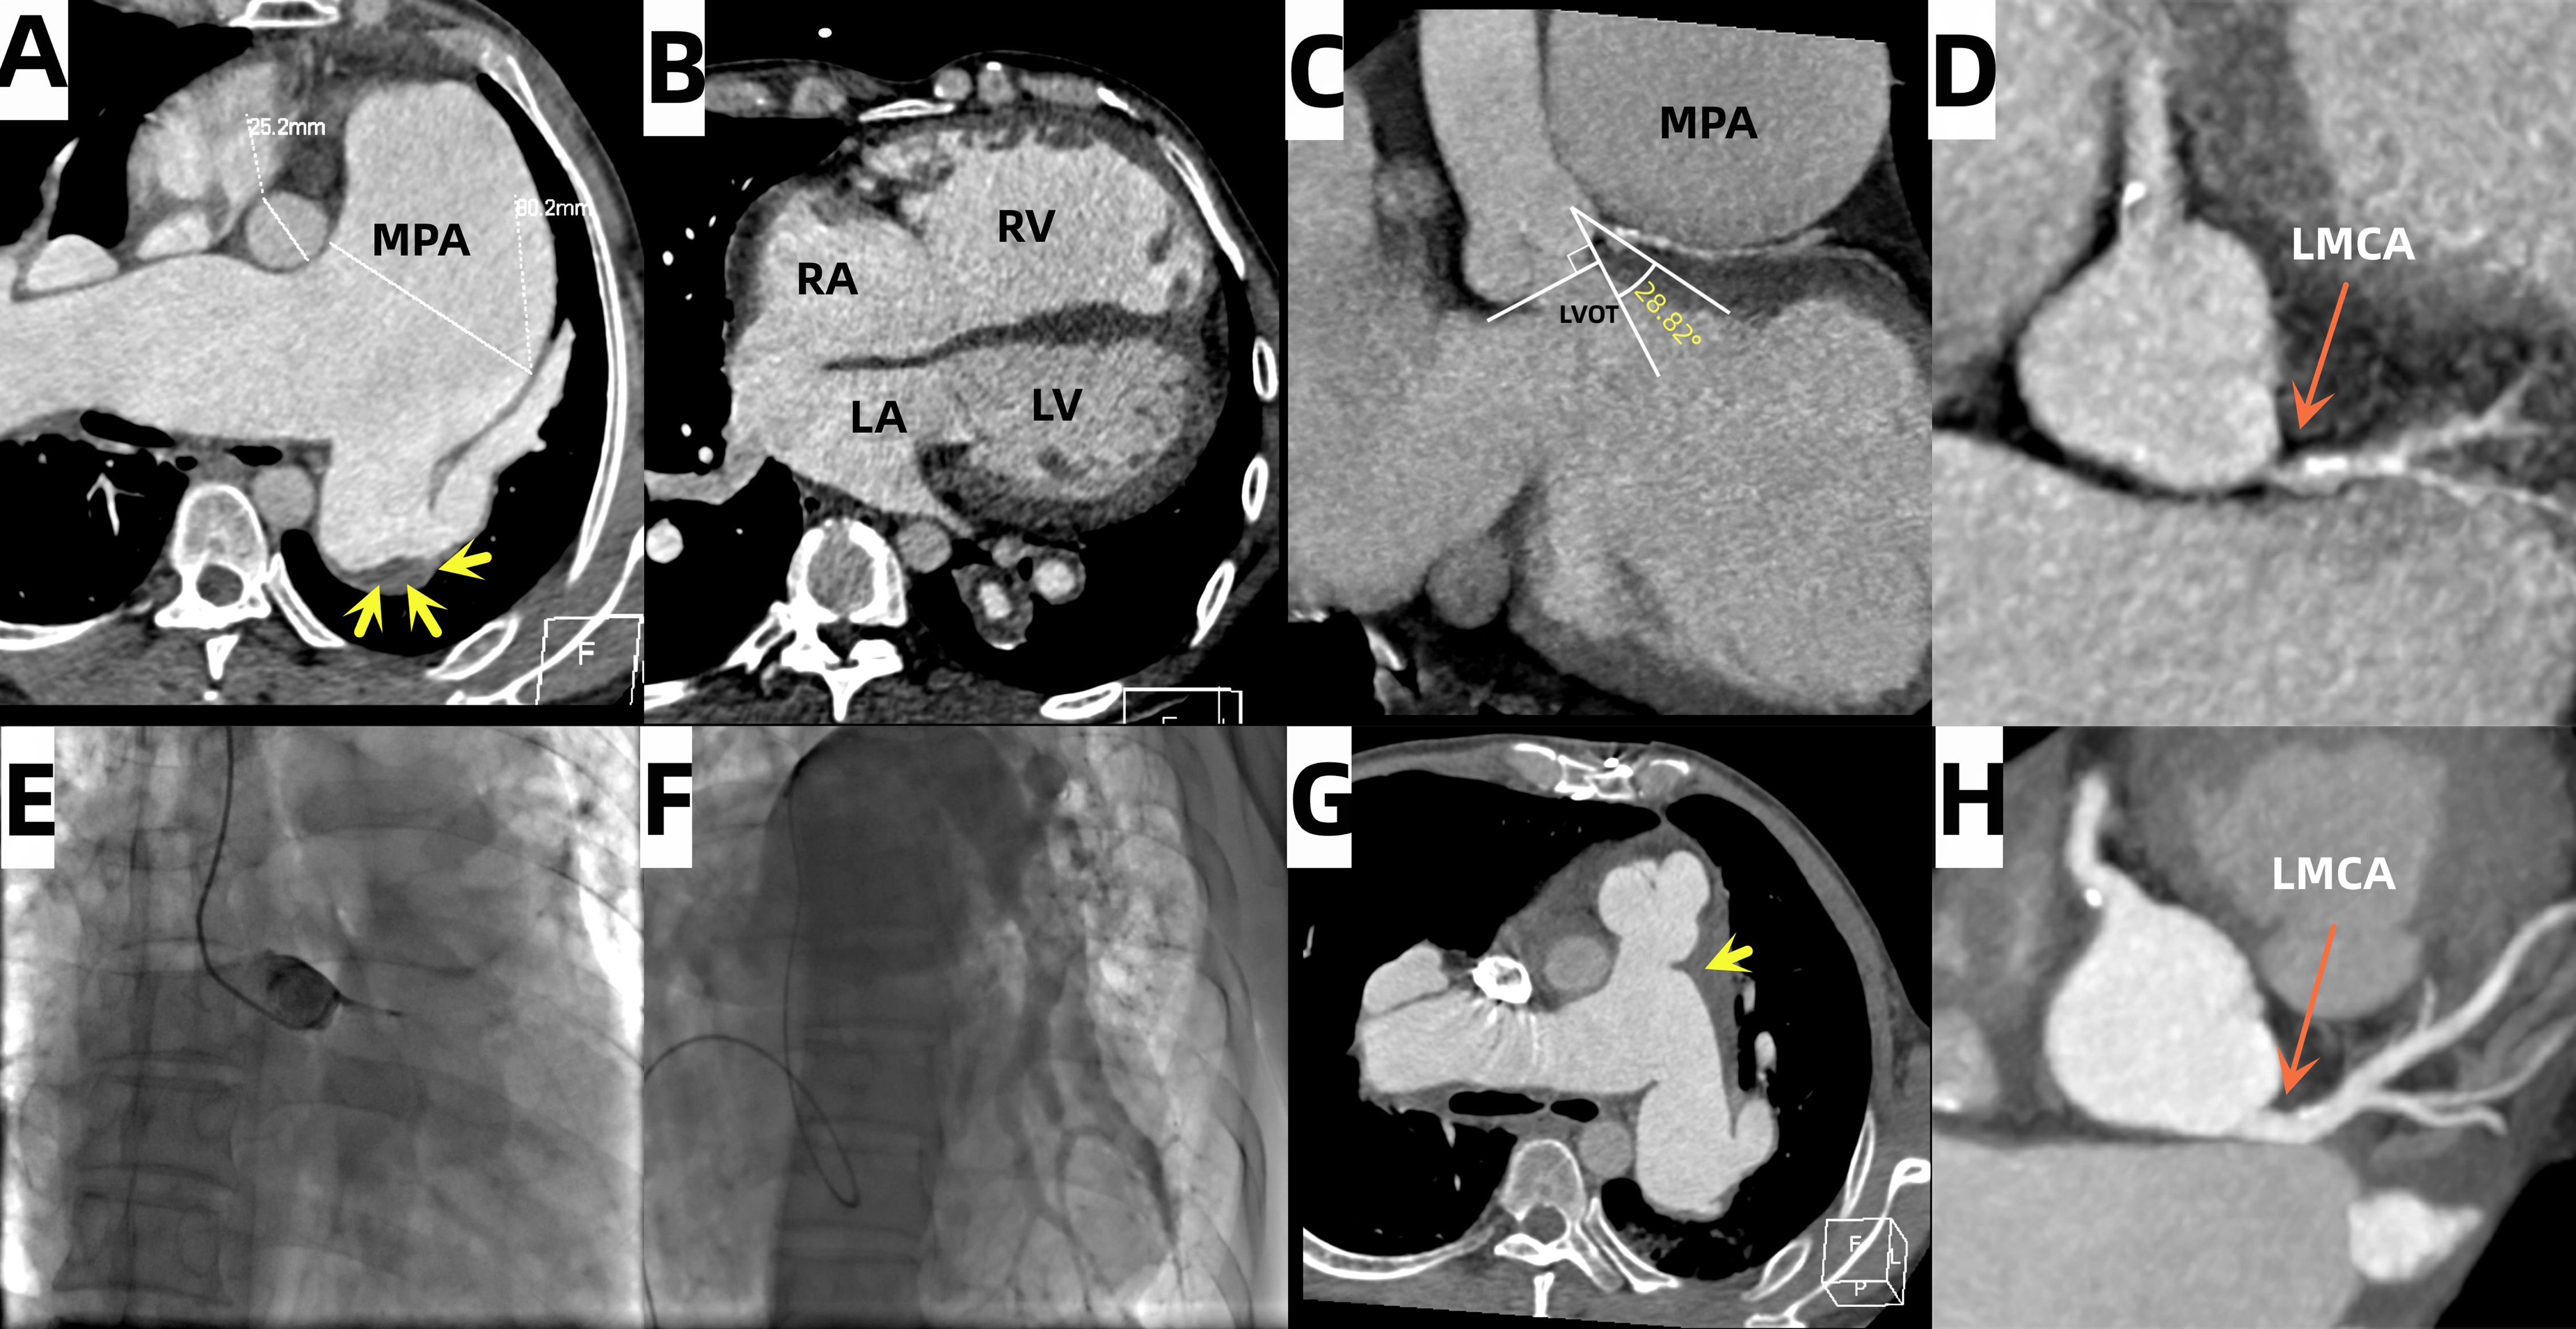

Computed tomography (CT) revealed a mixed ASD and an 80-mm pulmonary artery aneurysm (PAA) (Figure A and B), as well as subtotal occlusion of the left main coronary artery (LMCA) with a take-off angle of less than 60° (Figure C and D) and pulmonary artery (PA) thrombosis in the left inferior pulmonary artery (Figure A). Coronary angiography confirmed the subtotal occlusion of the LMCA and collateral circulation from the right coronary artery (Figure E, Videos 1 and 2). Cardiac catheterization demonstrated a mean PA pressure of 53 mm Hg and stenosis of the lower left PA (Figure F, Video 3).

The patient successfully underwent PA reconstruction surgery and removal of the thrombus from the left PA (Figure G). The coronary artery stenosis was completely resolved after the surgery (Figure H). After 1 year of oral therapy for heart failure associated with PAH, his PA pressure decreased to 36 mm Hg.